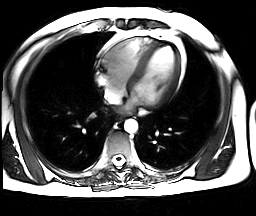

A medida pela ecocardiografia da superfície de corte do arco aórtico (ou, alternativamente, dá área da aorta descendente), combinada com a velocidade de fluxo, permite o cálculo do débito cardíaco.